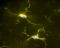

Mikroglia

Mikroglia/-/microglia

Der kleinste Typ der Gliazellen ist Teil des zellulären Immunsystems und unter anderem zuständig für die Entfernung abgestorbener Neurone. Mikroglia können sich amöbenartig fortbewegen.